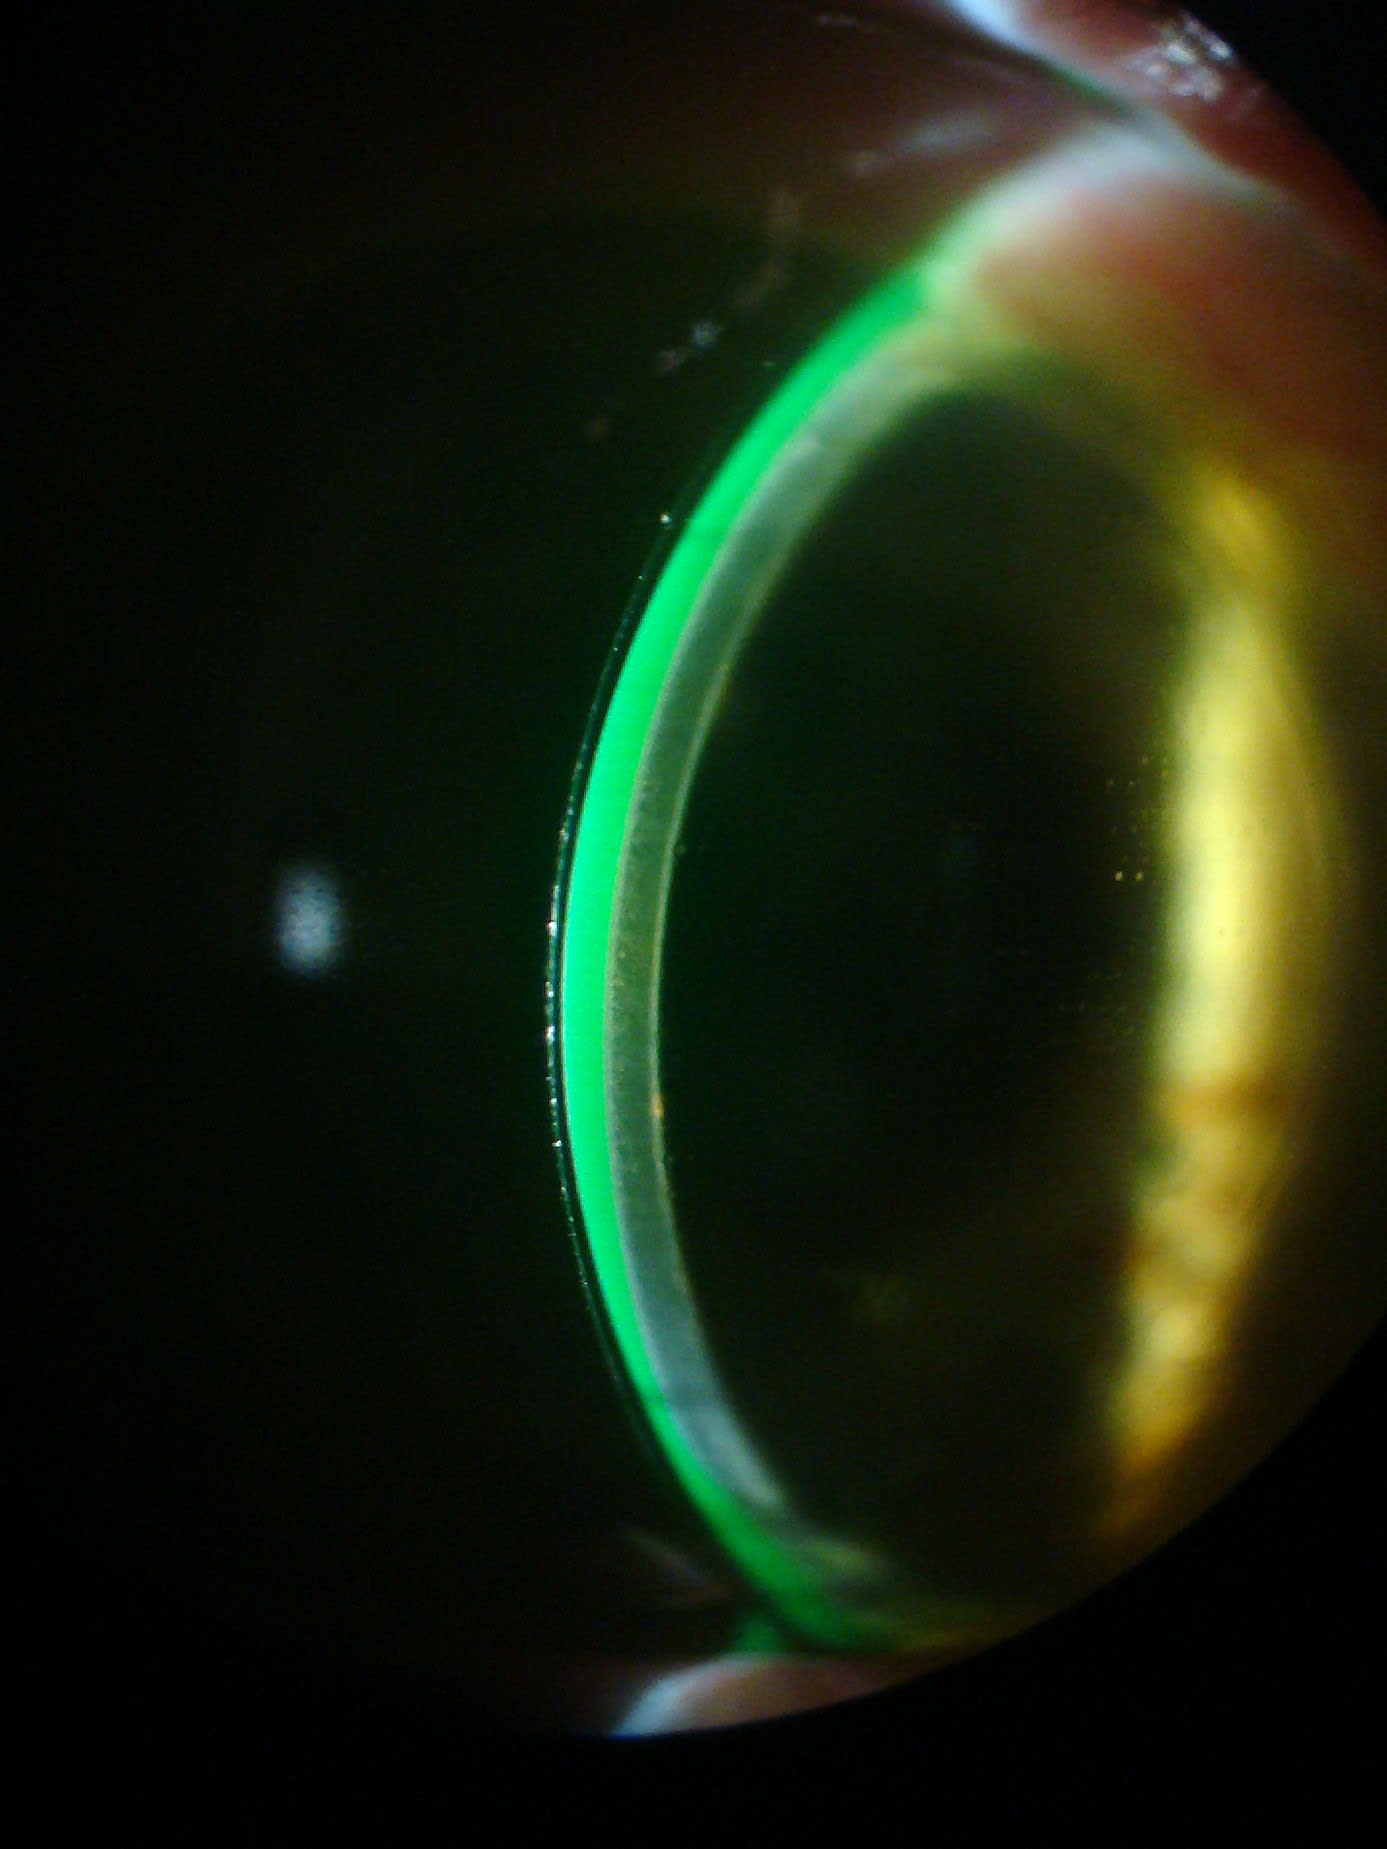

In this patient, prolapse was likely exacerbated by excessive superior vault. The large amount of superior vault was due to high overall vault and a landing zone transition not optimized for the shape of the corneal graft to sclera (Figure 2).

Vault was reduced centrally by 253 μm and increased at the midperiphery. The haptic was shortened and realigned closer to the limbus (Figures 6 to 8). Early improvement in prolapse was noted; further assessment will follow lens settling.

After lens settling, less clearance was expected. Observation right after lens application still showed high overall, but more uniform clearance (Figure 9).